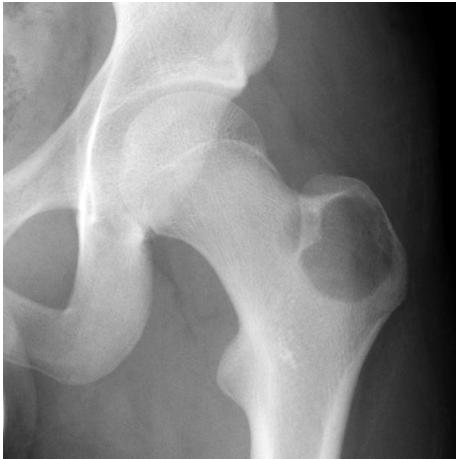

AP/Posterior left femur

- Site: Extra-capsular proximal femur greater trochantric

- Size: 4x3cm apple shaped

- Matrix: Radiolucent,

- Zone of transition: narrow zone of transition

- Bone effect:

- Soft tissue: i cant appreciate soft tissue involvement

most likely benign